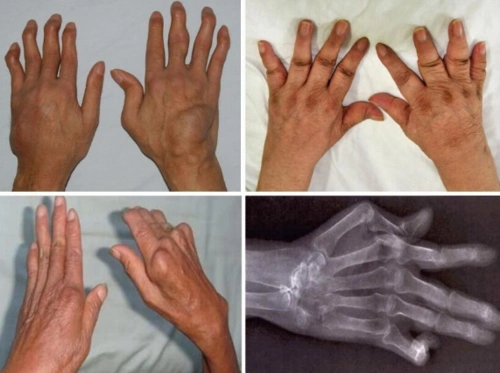

类风湿性关节炎患者通常还会出现关节肿胀,疼痛,畸形的症状. 4,皮下